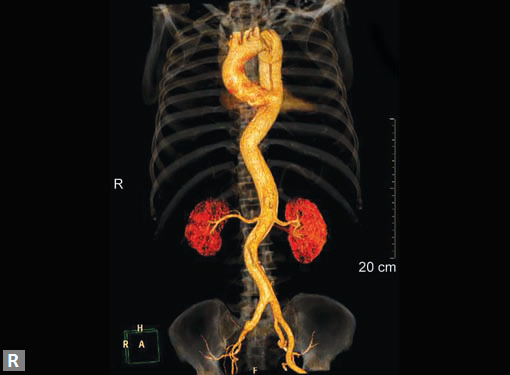

Any part of aorta can get affected by aneurysms. Focal

dilations can be saccular or fusiform. Atherosclerosis is

the most common cause. Tubercular and other infective

aneurysms, traumatic ones are also uncommonly seen. Size

of the aneurysm, proximity to origin of main vessels, relation

with branching and bifurcation, presence of mural thrombus

are the critical information sought on CT.

Contained leak, rupture are the feared complications.

Aortoenteric fistula is a rare but potentially catastrophic

complication. Aneurysmal dilation is common in ascending

aorta (Figs 19W to Y).

CT is also useful in surveillance of diagnosed aneurysms.

Figs 19A to Y (A to C) Scannogram (A), plain (B) and contrast study (C) show partial anomalous pulmonary venous connection; (D to F) Heterotaxy; (G) Aortic occlusion; (H and I) Aortic stents; (J) Aortic dissection with ‘Benz’ sign due to second dissection within the true lumen; (K, L and M) Aortic dissection with thrombus in pseudolumen following catheter angiogram; (N) Aortic dissection involving common carotid arteries and subclavian artery; (O, P, Q and R) Aortic dissection with right renal artery arising from true lumen and left renal artery from false lumen; (S, T, U and V) Stanford B dissection with extension Y to iliac vessels; (W to Y) Aneurysmal dilation of ascending aorta